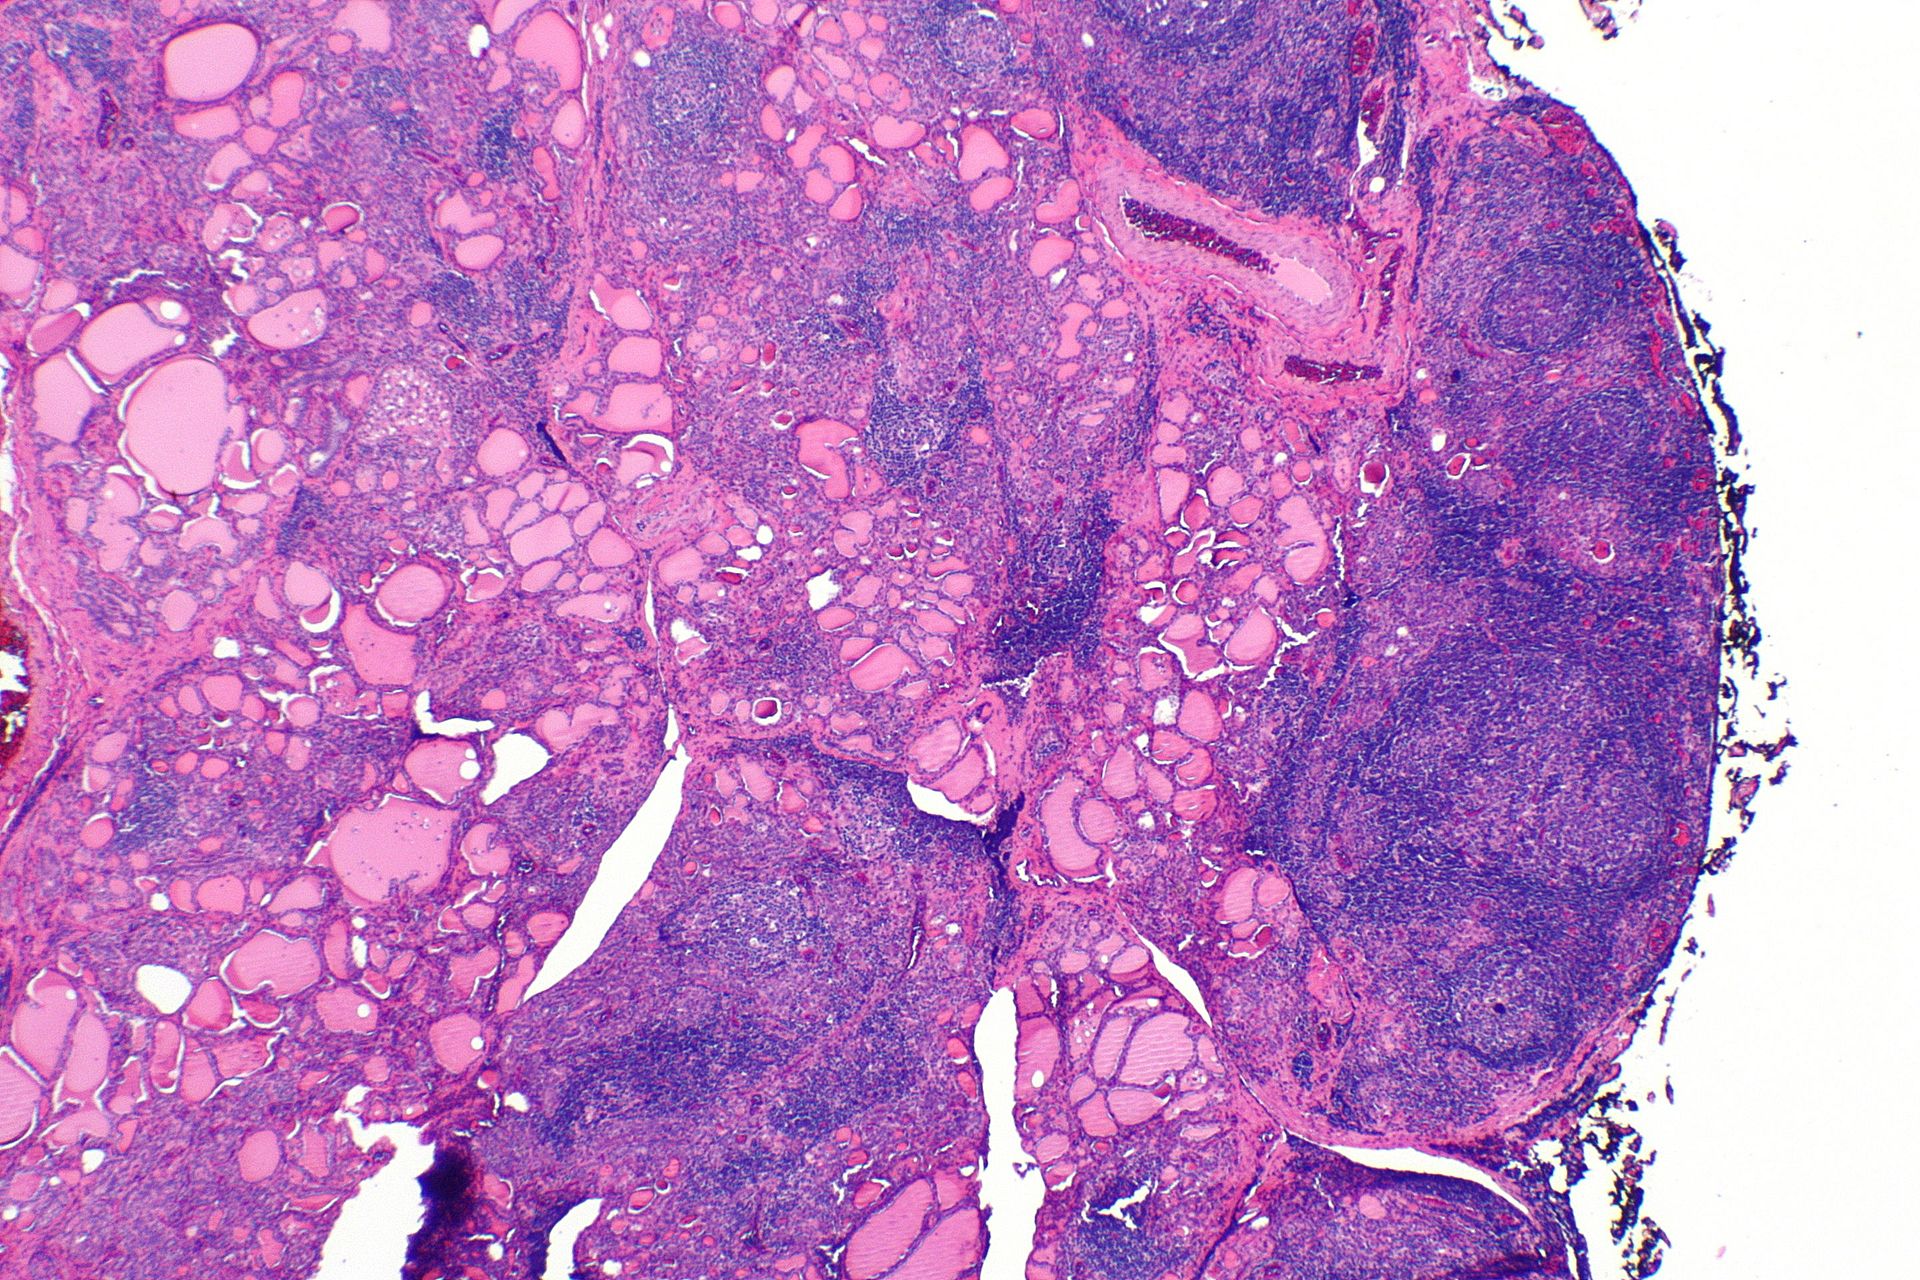

Что такое туберкулез щитовидной железы - фото презентация